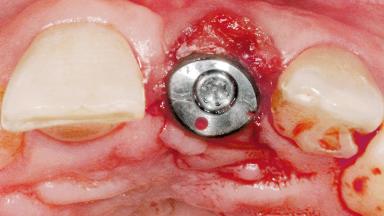

Late Flapless Placement of an Implant in a Maxillary Left Central Incisor Site

A 39-year-old male patient presented with a chief complaint of discomfort and gingival discoloration around his maxillary left central incisor. He was in good general health and was a non-smoker. His past dental history was significant because of the traumatic fracture of tooth 21 in a sporting accident at age 13. Initial dental treatment included endodontic therapy and a full-coverage restoration. The patient became symptomatic 5 years later, when structural failure of the tooth resulted in the dislodgment of the crown. Endodontic retreatment, apical surgery, and post-and-core restoration were performed.

Bone Augmentation Horizontal|Staged

Soft Tissue Grafting Simultaneous